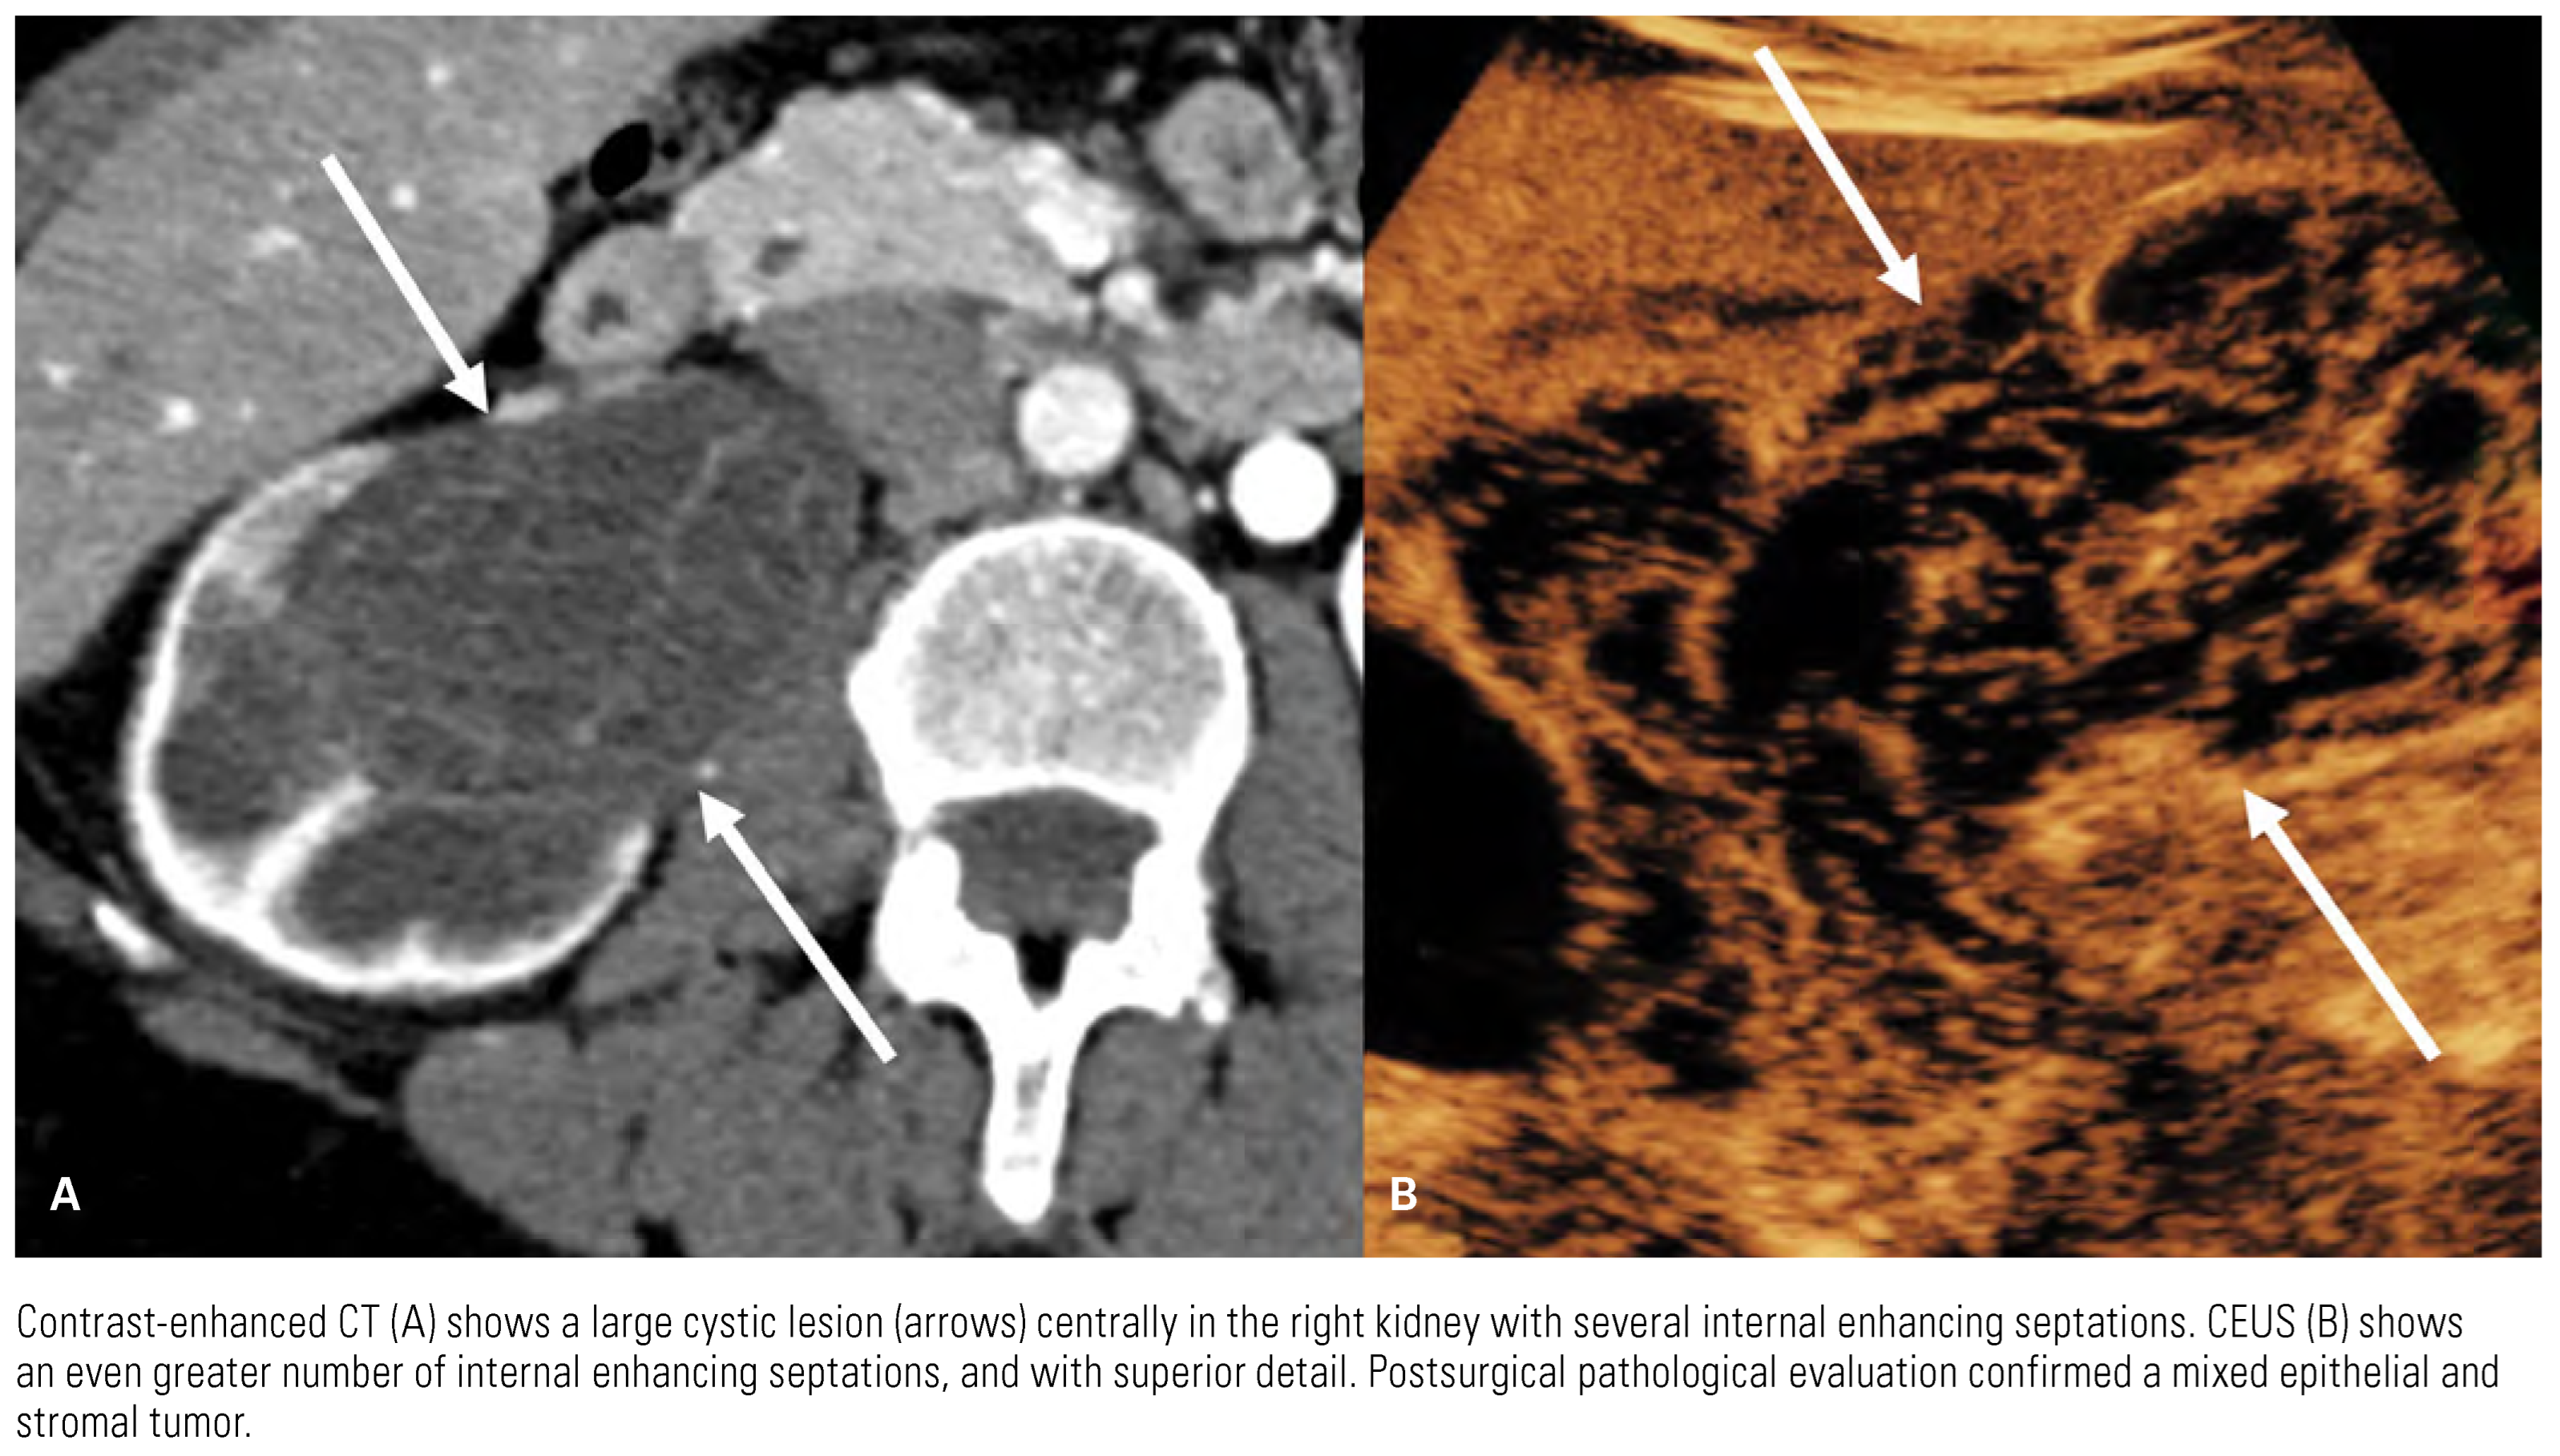

![]() |